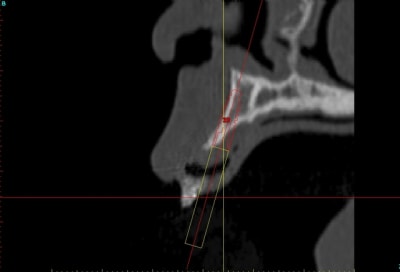

voilà, j'ai trouvé 5 mn...

le projet simplant est théorique, ça ne correspond pas à ce qui sera posé, c'était pour étude.

Fred à fait une séance d'ostéo-tension et 21 jours plus tard je me suis déplacé chez lui pour effectuer une deuxième séance, (nous avions adapté le protocole pour ce cas, 2 fois 21 jours au lieu de 40), afin de préparer le site et d'avoir une bonne connaissance du type d'os que nous allions trouver.